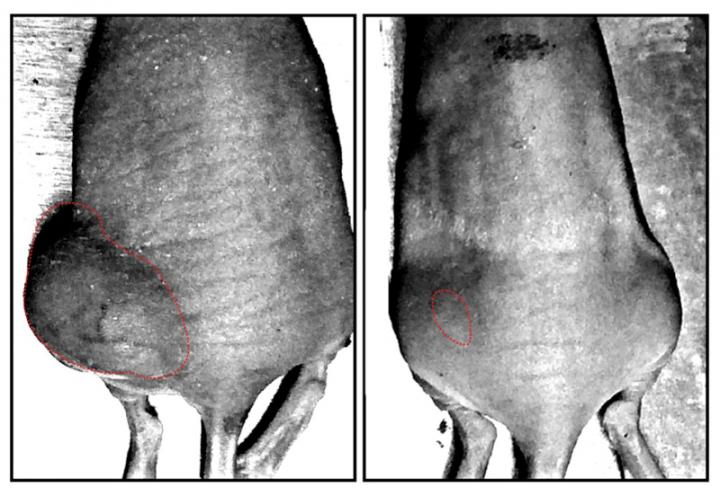

The research group of Professor Masaharu Noda and Researcher Akihiro Fujikawa of the National Institute for Basic Biology (NIBB) showed that the enzymatic activity of PTPRZ is requisite for the maintenance of stem cell properties and tumorigenicity in glioblastoma cells. PTPRZ knockdown strongly inhibited tumor growth of C6 glioblastoma cells in a mouse xenograft model. In addition, the research team discovered NAZ2329, an allosteric inhibitor of PTPRZ, in collaboration with ASUBIO Pharma Co. Ltd.. NAZ2329 efficiently suppressed stem cell-like properties of glioblastoma cells in culture, and tumor growth in C6 glioblastoma xenografts. These results indicate that pharmacological inhibition of PTPRZ is a promising strategy for the treatment of malignant gliomas.